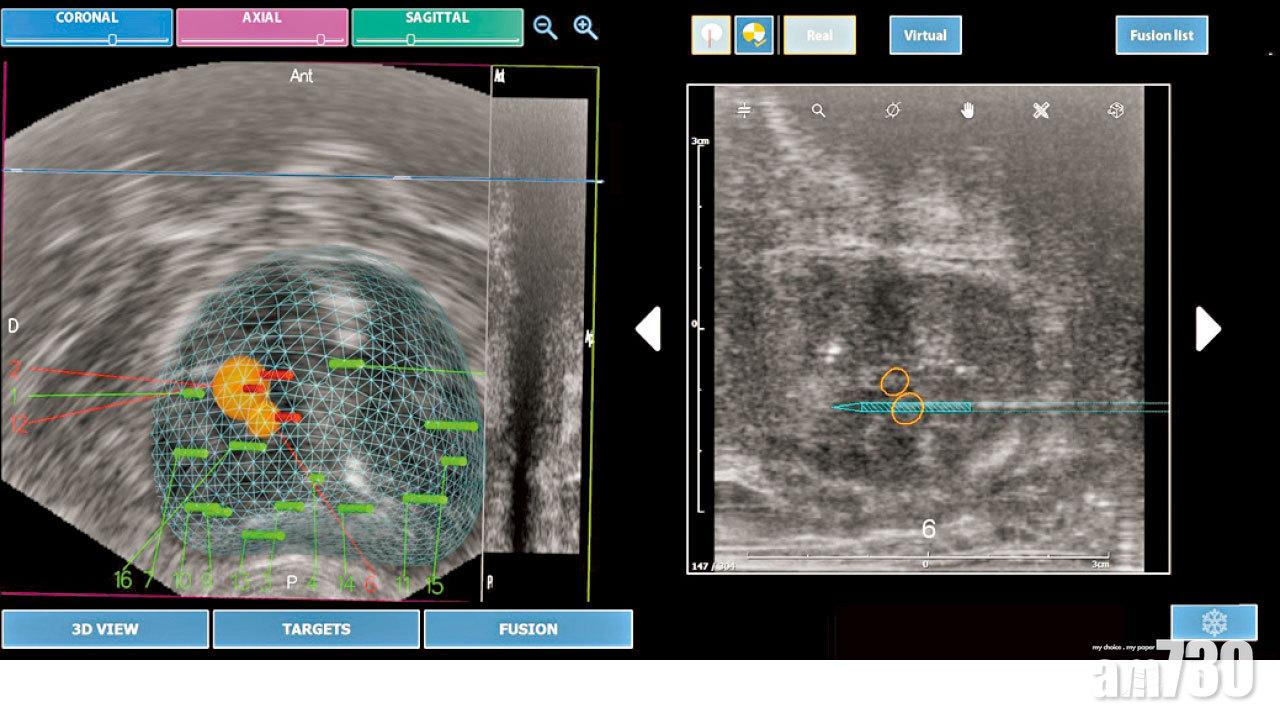

以前沒有融合技術,醫生主要靠自己的經驗及超聲波的影像引導,估計懷疑有前列腺腫瘤的位置抽針。可是,在抽針觸碰前列腺時,前列腺會隨之變形,影響落針的準確度。特別是當前列腺腫瘤體積較小的時候,抽針過程便有可能出現誤差。後來發展出將MRI及超聲波兩者影像融合技術,讓醫生更準確知道前列腺腫瘤的位置,不但增加抽針的準確度,更提高之後手術治療的成功率,增加病人存活機會。

利用融合技術將超波聲和磁力共振影像結合將前列腺腫瘤定位,再配合微波或HI-FU治療,大大提高治療成效。